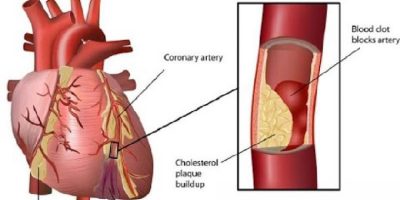

আপনি যদি ধারণা করে থাকেন হার্ট অ্যাটাকের মতো কিছু রোগ শুধু দ্রুত মৃত্যু ঘটায়, তাহলে আরো কিছু রোগ রয়েছে যা আপনাকে চোখ মেলে দেখতে হবে।

এ প্রতিবেদনে জীবননাশক দশটি রোগ উল্লেখ করা হলো, যা ২৪ ঘণ্টার মধ্যে মানুষের মৃত্যু ডেকে আনতে পারে।

সেরিব্রোভাসকুলার রোগ

এ রোগের শিকার ব্যক্তির শরীরে প্রয়োজনীয় পুষ্টি ও অক্সিজেন বিচ্ছিন্ন হবার ফলে রোগী মৃত্যু কিংবা স্থায়ীভাবে নিস্ক্রিয় হয়ে যেতে পারে। ৩-৬ ঘণ্টার মধ্যে চিকিৎসা না করালে মারাত্মক রুপ নিতে পারে। রোগীর মুখে অসাড়তা দেখা যায় এবং মাথা ঘোরে। আক্রান্ত ব্যক্তি সাধারণত অন্ধ হয়ে যায় এবং কথা বলতে পারে না। মস্তিষ্কের ফাংশন অক্ষত থেকে মাথা থেকে অঙ্গুলী পক্ষাঘাত হয়।

চাগাস রোগ

এ রোগবাহী এক ধরনের রক্তচোষা পোকা মানুষের শরীরে কামড় দিলেই জীবাণু সংক্রমিত হয়। এটি শরীরের কার্ডিওভাসকুলার সিস্টেম ধ্বংস করে দেয়। রোগী সাধারণত উপলব্ধি করতে পারেন না, তবে দ্রুত চিকিৎসা না দিলে আকস্মিক মৃত্যু ঘটাতে পারে।